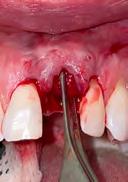

3. Minimally invasive removal of #12 using only a buccal approach mini-flap showing an intact buccal plate with immediate placement of the implant (1 mm below the intact buccal wall) in a screw-retained position. A 3mm buccal gap is measured and a 1.5mm palatal gap.

4. Both the buccal and palatal gaps have been packed with Geistlich Bio-Oss Collagen® hydrated with Gem 21S. I prefer to squeeze Geistlich Fibro-Gide® between thumb and forefinger, prior to placement. A dry-carved piece of Geistlich FibroGide® is in position thinned approximately 2mm with beveling laterally and coronally with a new #15 blade.

5. Geistlich Fibro-Gide® in place facial to the intact buccal wall under a full thickness buccal approach mini-flap. Immediate contour management was completed using an Anatotemp® for a maxillary bicuspid tooth.